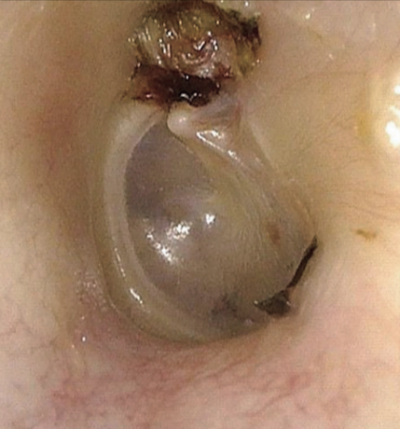

36 歳の女性。左耳の聞こえにくさを主訴に来院した。数年前から左耳漏を繰り返していた。最近、聴力が低下してきたため受診した。左鼓膜所見と側頭骨単純 CT の冠状断像を別に示す。

治療として適切なのはどれか。